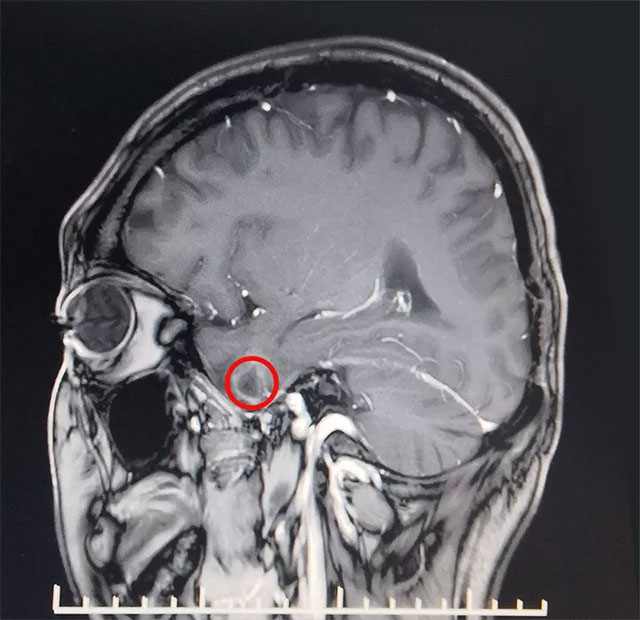

▲ 患者致癲灶位置

近期,上海藍(lán)十字腦科醫(yī)院功能神經(jīng)外科收治了一名外傷繼發(fā)性癲癇患者,通過(guò)綜合運(yùn)用磁共振、24小時(shí)長(zhǎng)程視頻腦電并結(jié)合臨床病史等最終精準(zhǔn)定位致癲灶,并成功為其手術(shù)切除。

患者王先生27歲,自13歲時(shí)首次發(fā)病,經(jīng)過(guò)長(zhǎng)期規(guī)律多種藥物治療效果不佳,期間嚴(yán)重時(shí)發(fā)作頻率多達(dá)七次到八次每天,常于情緒激動(dòng)、打牌及勞累時(shí)誘發(fā),確診為藥物難治性癲癇。經(jīng)過(guò)檢查,MRS示雙側(cè)海馬結(jié)構(gòu)異常,左側(cè)顳葉軟化灶形成。VEEG檢查可見(jiàn)異常波:左側(cè)大腦明顯異常,大量癲癇波,結(jié)合患者病史并綜合相關(guān)檢查最終確定癲癇病灶位于左側(cè)顳葉、海馬處。